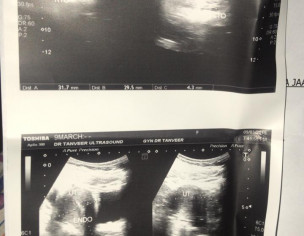

I have been feeling lethargic or rather too much distressed since the past couple of days on and off, i’m under no such stress, feel like the heart is sinking specially at night time and heaviness in the arms sp upper arms, around shoulders and specially palms and fingers and legs and somtimes too much tingling like pressure too as if its from within the veins. I have pcos. Have irregular menstrual almost evertime. cycle which exceeds 7 days sometimes if the hormones are acting up. Has happened once before last year that the discharge/bleeding continued for 20 days and this time around experiencing the same currently its the 10th day that it hasnt ended (its on and off). I’m attaching previous reports. Need expert advice. Thanks

what you have attached is not a report. Attach the reporting of ultrasound.

Attach Photo here: